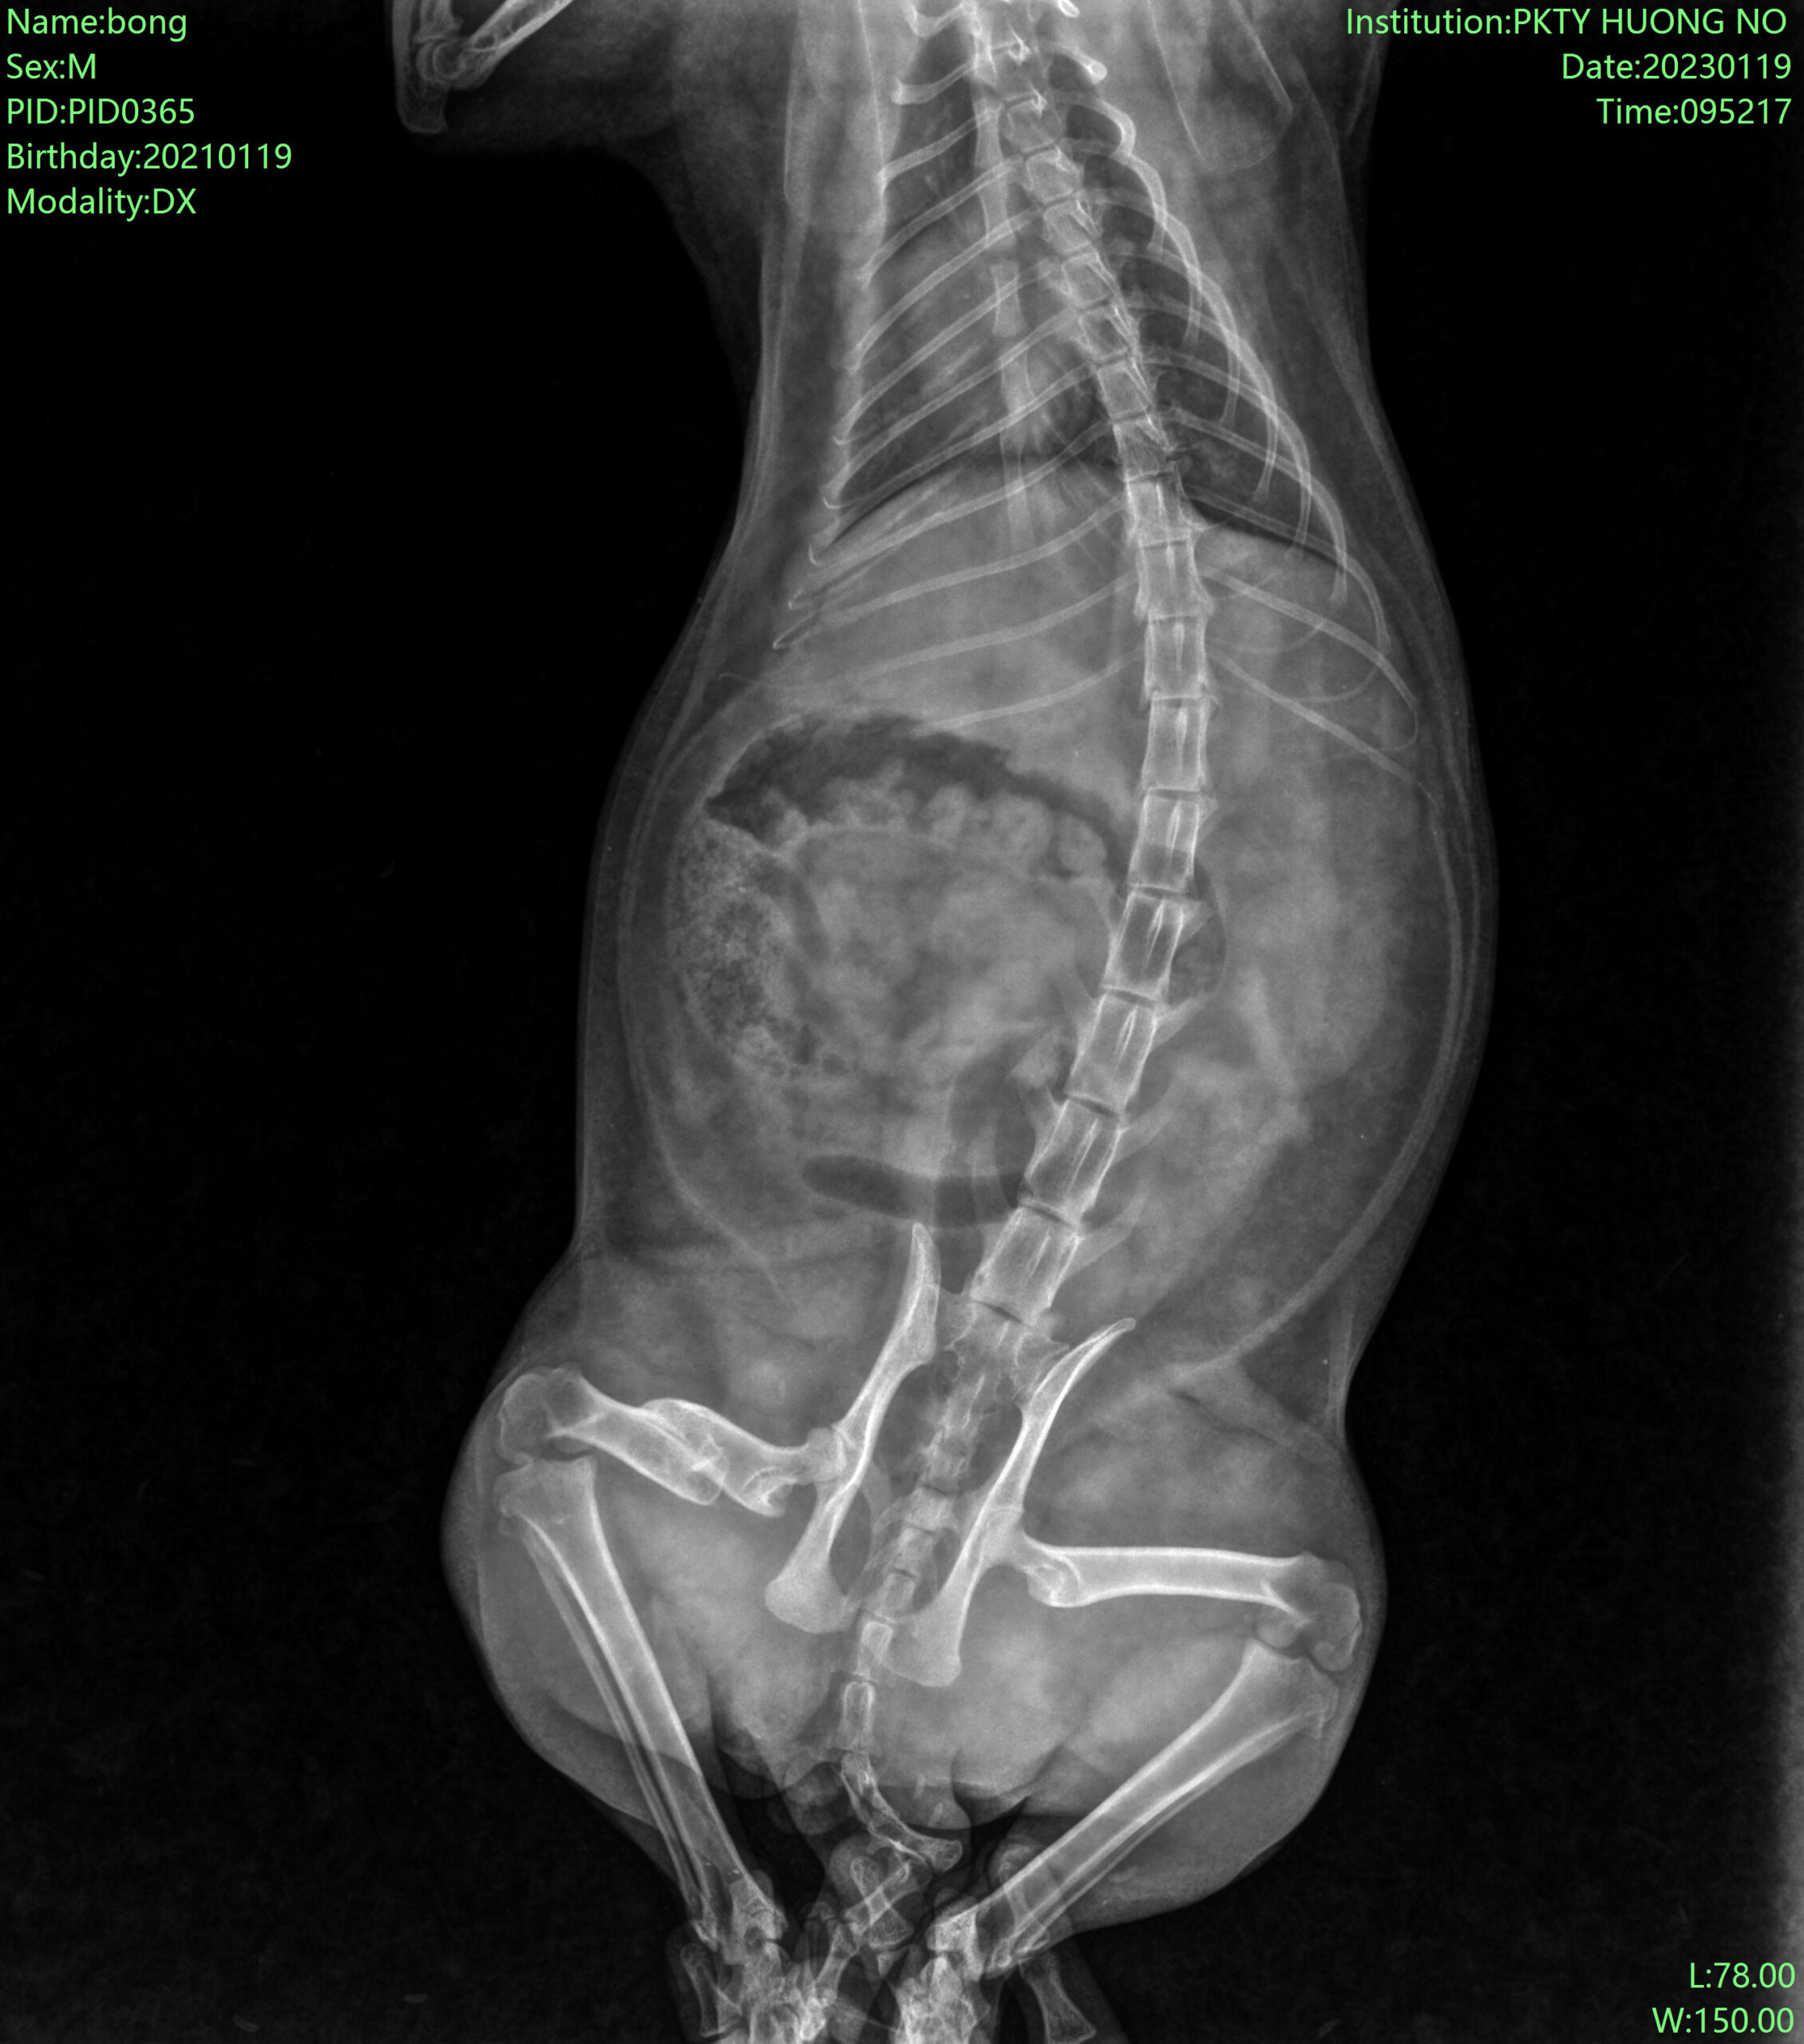

Trước phẫu thuật:

Sau phẫu thuật xuyên đinh: